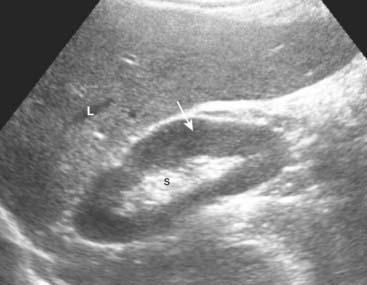

image The kidneys normally measure 9-12 cm in length, 4-5 cm in width, and are 3-4 cm thick. The renal sinus is home to the renal pelvis and the major branches of the renal artery and vein. Because the renal sinus contains fat, it normally appears brightly echogenic. The calyces are normally not visible. The medullary pyramids are hypoechoic. The renal parenchyma has uniformly low echogenicity, which is usually less than that of the adjacent liver and spleen (Fig. 19-9).

Figure 19-9 Normal right kidney, sagittal view.

The renal sinus (S) is home to the renal pelvis and the major branches of the renal artery and vein. Because the renal sinus contains fat, it normally appears brightly echogenic. The normal renal pelvis is not visible in the renal sinus. The renal parenchyma (solid white arrow) has uniformly low echogenicity and is usually less echogenic than the adjacent liver (L) or spleen.